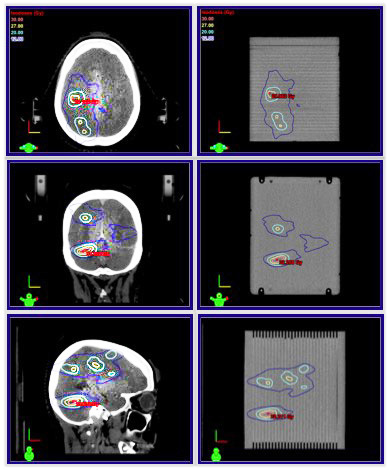

Cirs 037多病變腦QA模型,Cirs 037多病灶SRS治療計劃QA模體,Multi-Lesion Brain QA Phantom為具有多個靶標的單個等中心計劃提供了快速、全面的薄膜劑量學質(zhì)量保證的獨特解決方案。該模型可用于徹底驗證多病變治療方法

Cirs 037多病變腦QA模型,Cirs 037多病灶SRS治療計劃QA模體型呈矩形,圓角可最大限度地減少 CT 偽影,并且尺寸足夠大以覆蓋腦解剖結構變化。模擬腦組織的線性衰減在真實組織的 1% 以內(nèi),從 50 keV 到 15 MeV。

該模型具有兩對不對稱嵌入基準標記,并在模型等中心處將中心基準分成兩半,以在照射前成像期間為您提供幫助。您還可以對齊成像基準點(來自 CBCT、ExacTrac® 或 kV 圖像),并將它們與模型的參考圖像進行比較,以便更準確地將模型與直線加速器沙發(fā)頂部進行位移。

該模型以 5 毫米的增量接收多達 29 個位置的放射致變色膠片。預裝聚酯薄膜片可在不影響敏感幾何形狀的情況下靈活地放置薄膜?;糜皞让娴耐獠堪疾酆蜆擞浻兄趯⒈∧ぽp松定位在所需位置,以覆蓋特定病變。膠片允許單獨審查多個計劃目標卷 (PTV)。

使用多病變腦模型簡化SIMT計劃的膠片QA